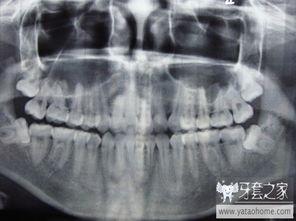

四、牙医的“魔法”:精准定位与巧妙操作

在拔阻生智齿的视频中,你会发现牙医们有着超凡的技艺。他们能够精准地定位智齿的位置,然后运用各种工具进行巧妙操作。有时候,他们会用牙挺将智齿撬出来;有时候,他们会用牙钳将智齿夹住,然后用力拔出。这个过程虽然痛苦,但却是必要的。